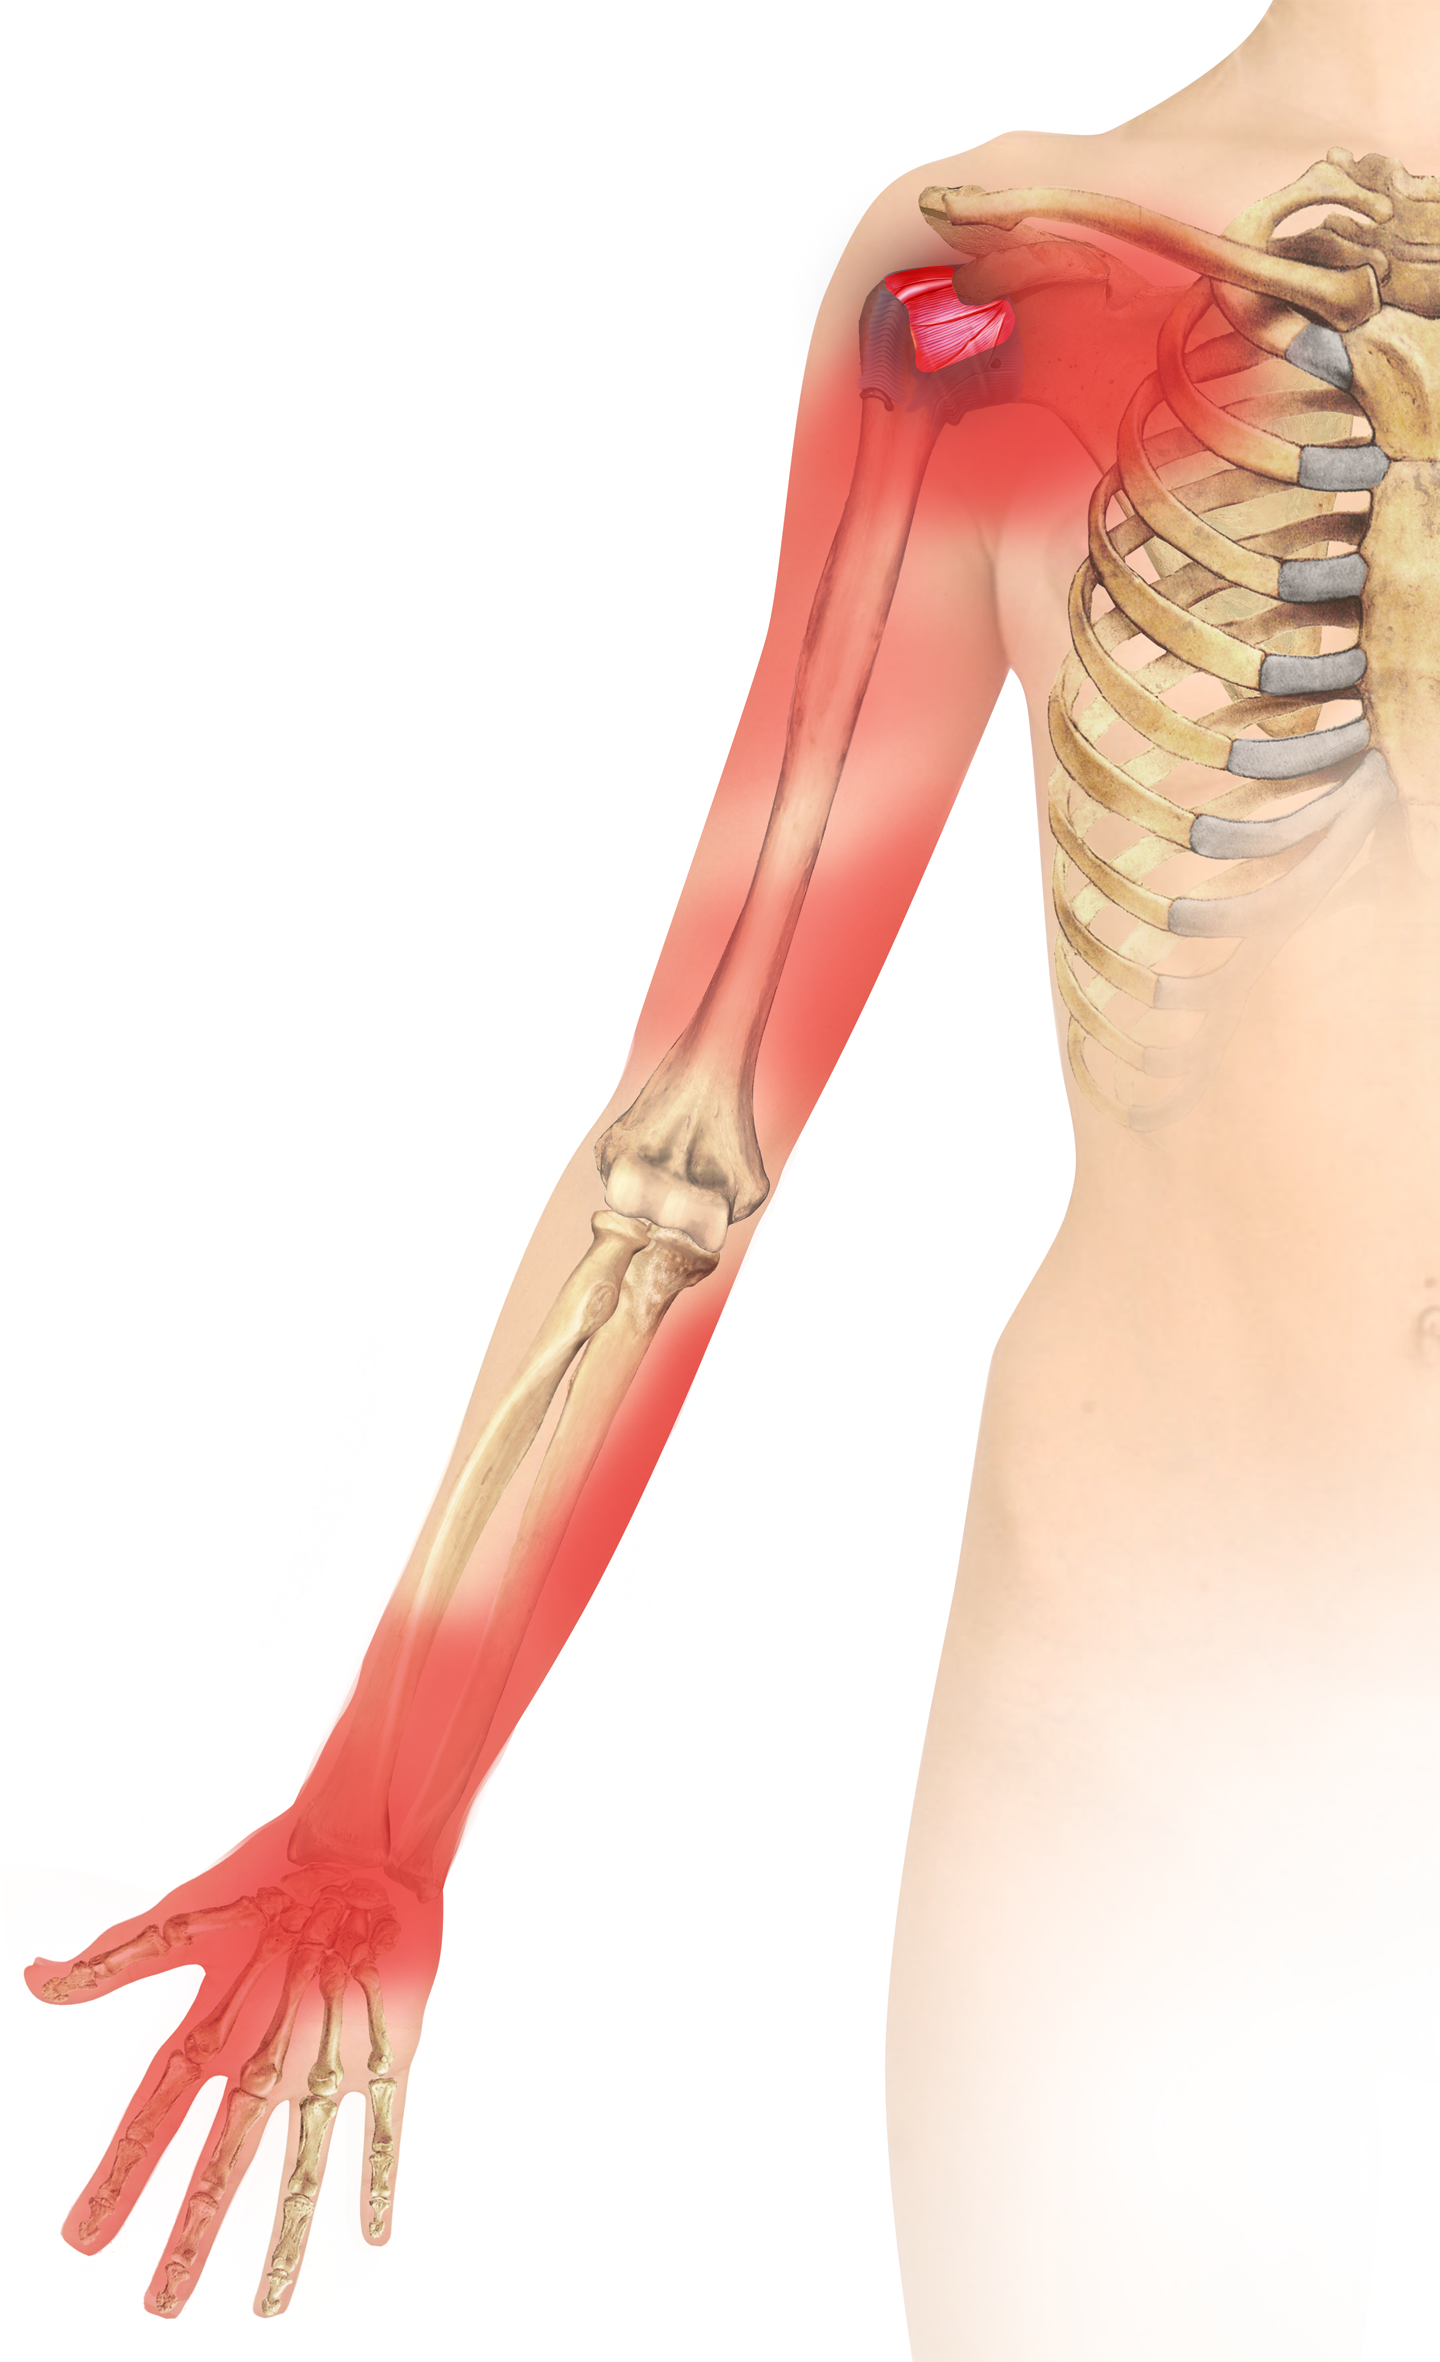

Glenohumeral ligament: анатомия и функции плечевого сустава